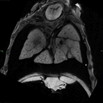

Caption Play MovieSerial 2D EFIC image stack in the coronal plane of 1526-007-NA reveals mirror image dextrocardia, biventricular hypertrophy, stenosis of transverse arch, and dual IVC

Copyright This image is from the Laboratory of Dr. Cecilia Lo, a member of the Cardiovascular Development Consortium (CvDC), Bench to Bassinet (B2B) program of the National Heart Lung and Blood Institute (NHLBI), and is displayed with the permission of the authors. J:175213

Dnai1b2b1526Clo dynein axonemal intermediate chain 1; Bench to Bassinet Program (B2B/CVDC), mutation 1526 Cecilia Lo

Dnai1b2b1526Clo/Dnai1b2b1526Clo C57BL/6J-Dnai1b2b1526Clo